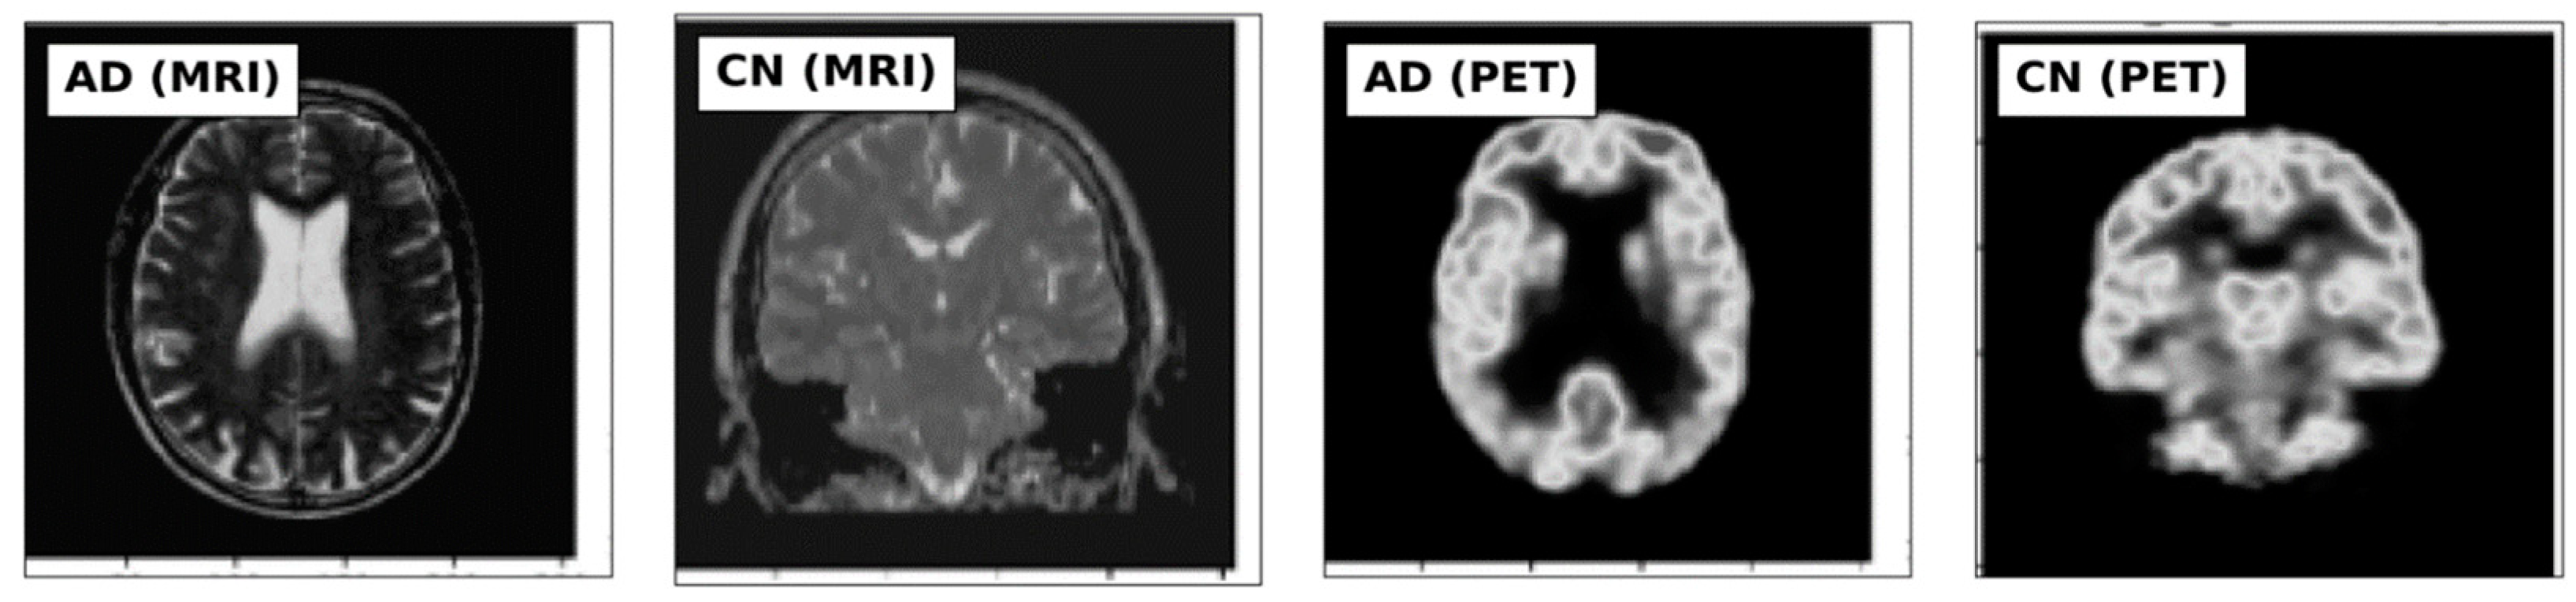

2.1. Datasets